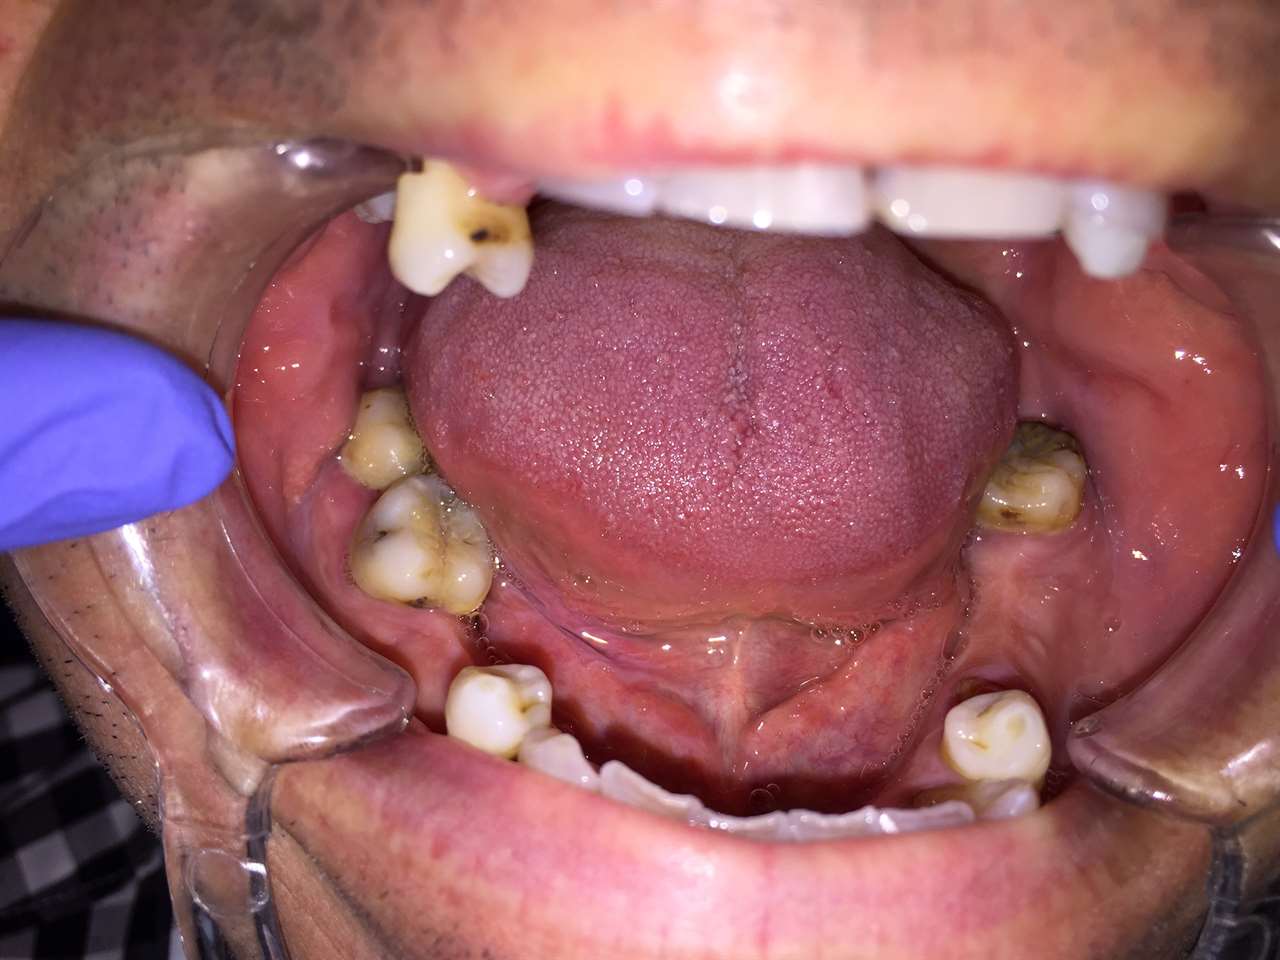

Elhanyagolt fogsor cseréje 2 nap alatt

2 nap alatt varázsoltuk ezt a szép esztétikus alsó, felső körhídat implantátumokkal megtámasztva a korábban elhanyagolt szájba. Az 1. nap 26 fogat távolítottunk el, mert annyira rossz állapotban voltak, és rögtön azonnal terhelhető IHDE svájci implantátumokat raktunk be, fentre 8, lentre 6 darabot. A sebeket összevarrtuk és intraorális szkennerrel digitális lenyomatot vettünk. 2 nap múlva pedig beragasztottuk a kész PMMA műanyag körhidakat. Dr. Kelemen Péter és a Symbion Fogtechnika munkája.